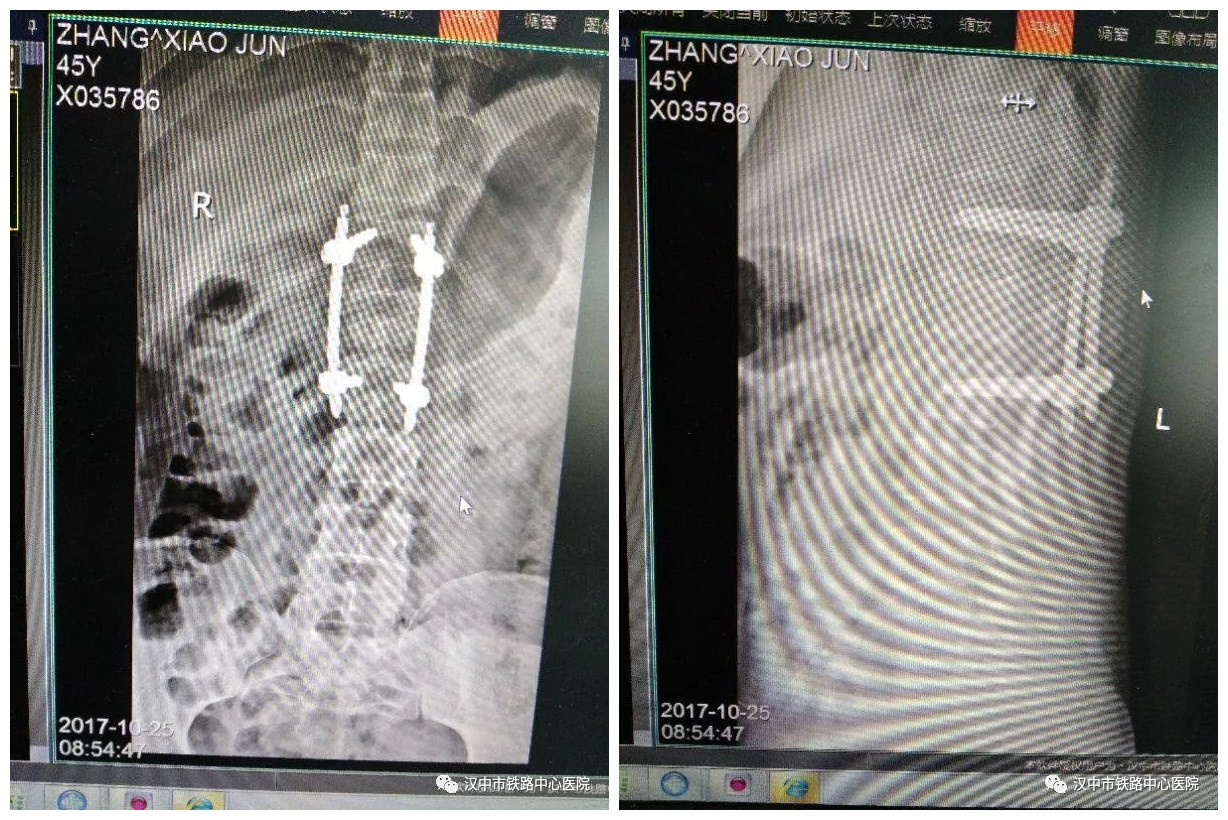

45岁的张先生是汉台区人,因从2米高处坠落臀部着地致腰背部疼痛、活动受限,诊断为腰1椎体压缩性骨折(II度)。10月19日,胡昭华博士主刀为其进行后路腰1椎体压缩性骨折经皮微创置钉内固定术,手术仅耗时两小时,术中出血仅20毫升。

术 后